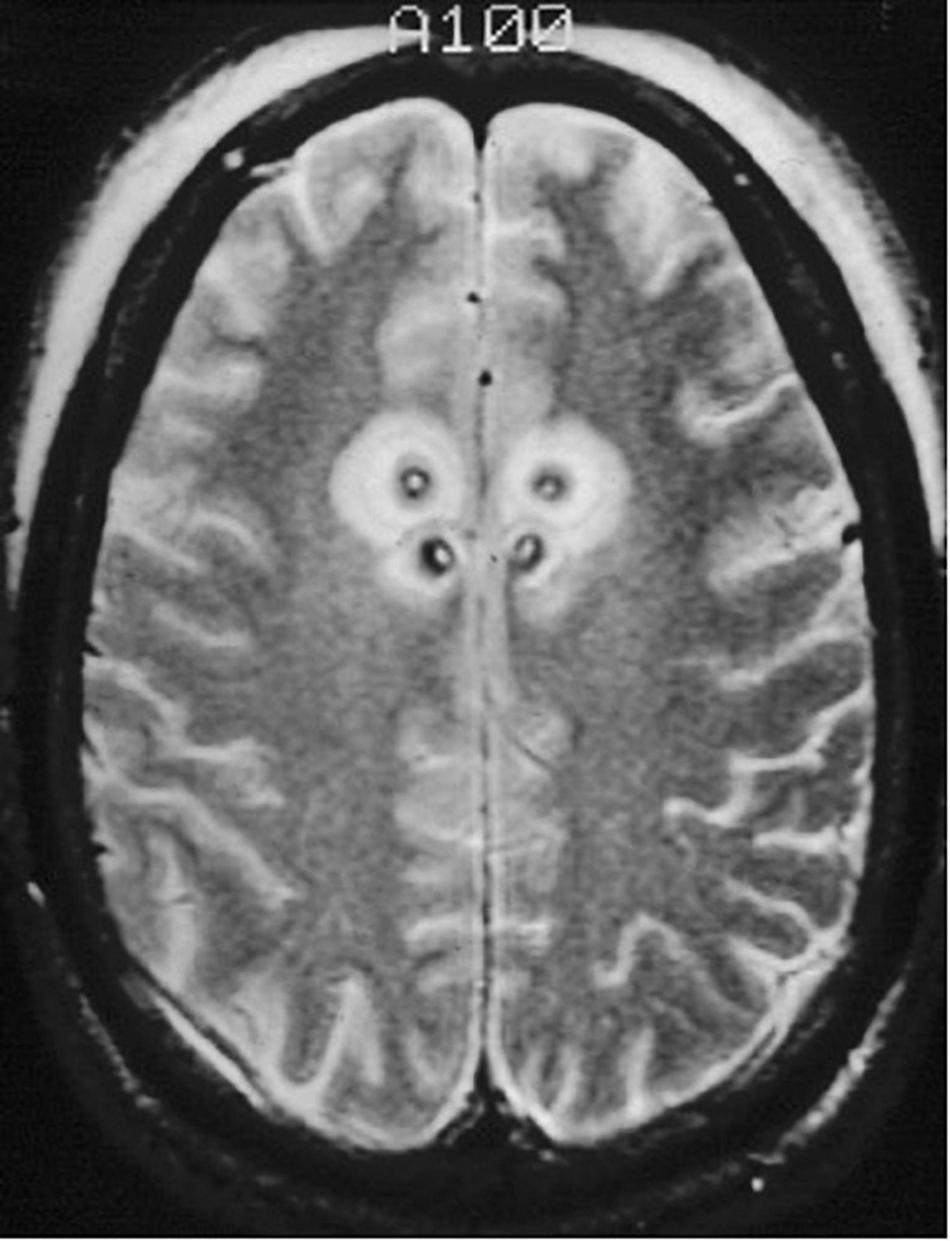

FIGURE 5

Staged cingulotomy. Transverse T2-weighted MRI of chronic (posterior) and acute (anterior) double cingulotomy lesions.